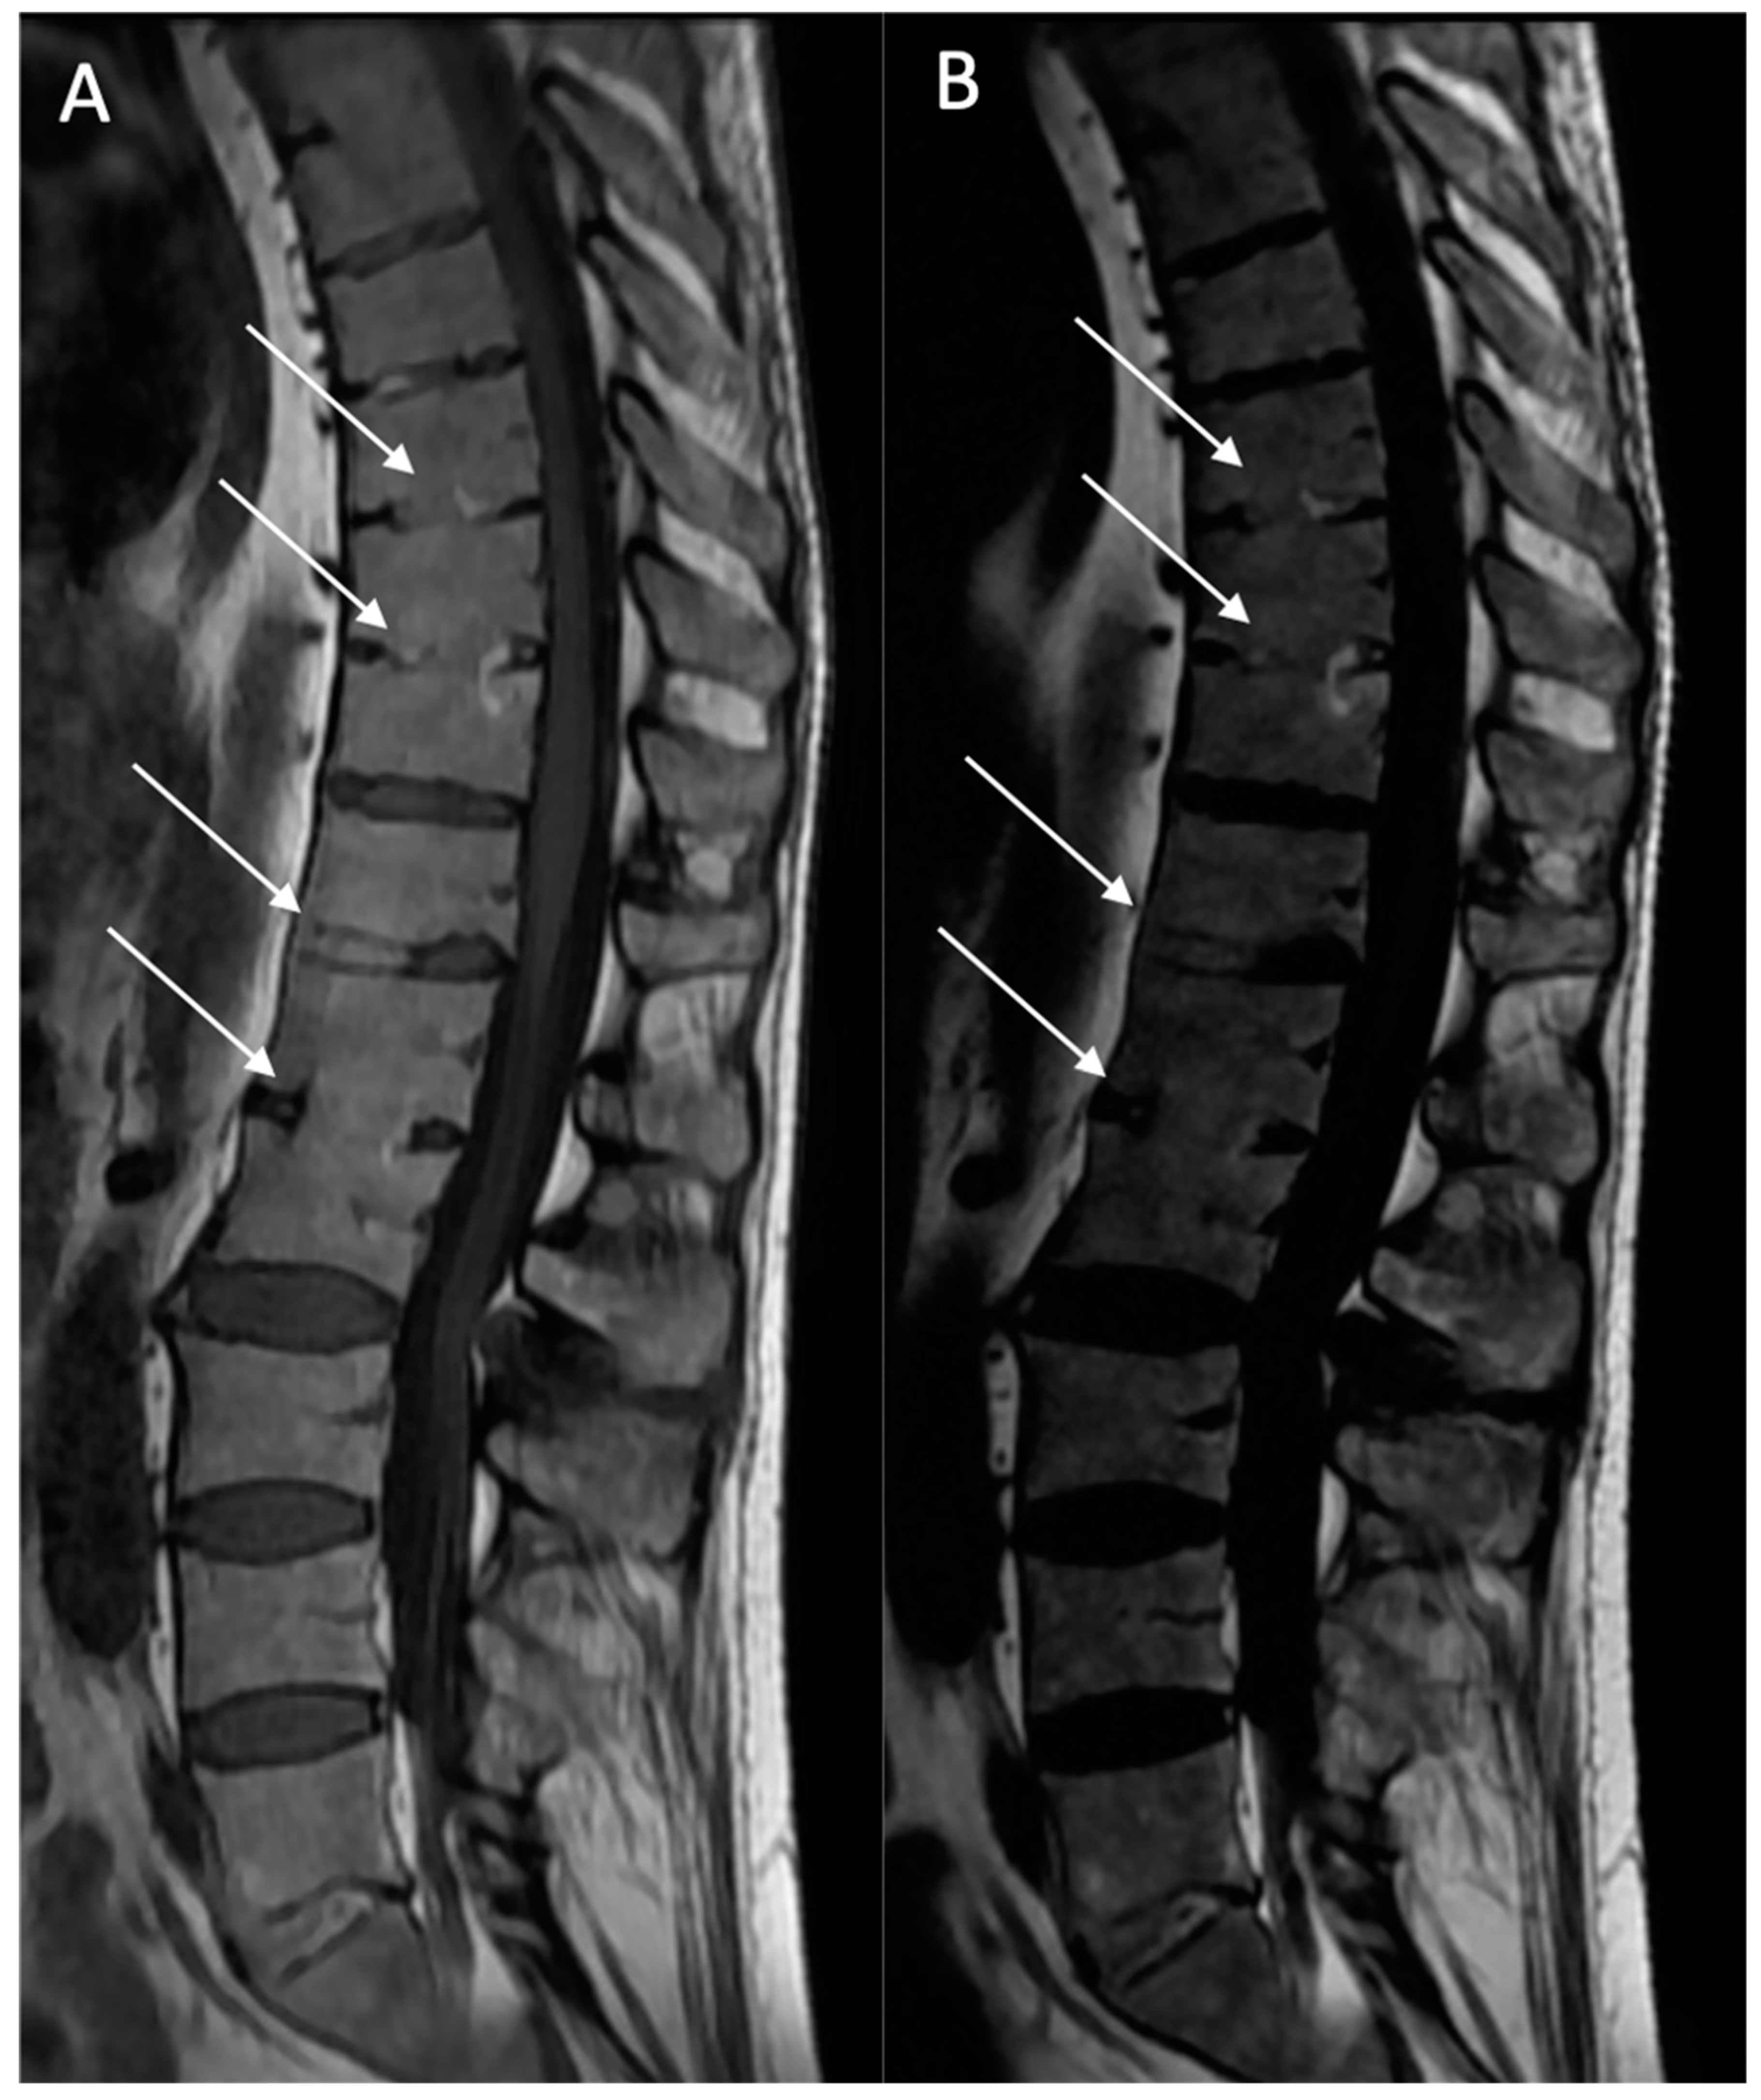

Structural erosions (BMEs): Defined as focal and ill-defined enthesis cortical defects that could be isolated or confluent, with a loss of the normal subchondral cortex appearance and broad irregular margins on both sequences (Figure 3).

Figure 3. Multiple fatty lesion (BMF) changes and erosions in a 61-year-old patient. A T1w sagittal sequence showing BMF localization mainly at the thoracic longitudinal ligamentary structure enthesis (arrows) (A). Focal erosion is noted at the L4 and L5 anterosuperior vertebral corner (circle), and appears as a focal hyposignal. A T2w Dixon (fat) image more clearly showing BMF localization (arrows). Erosion areas are surrounded by fatty replacement areas (B). A T2w STIR coronal oblique sequence showing left anterior inflammatory sacroiliitis (C). A T1w coronal oblique sequence showing structural changes with an erosive sacroiliac lesion (D).